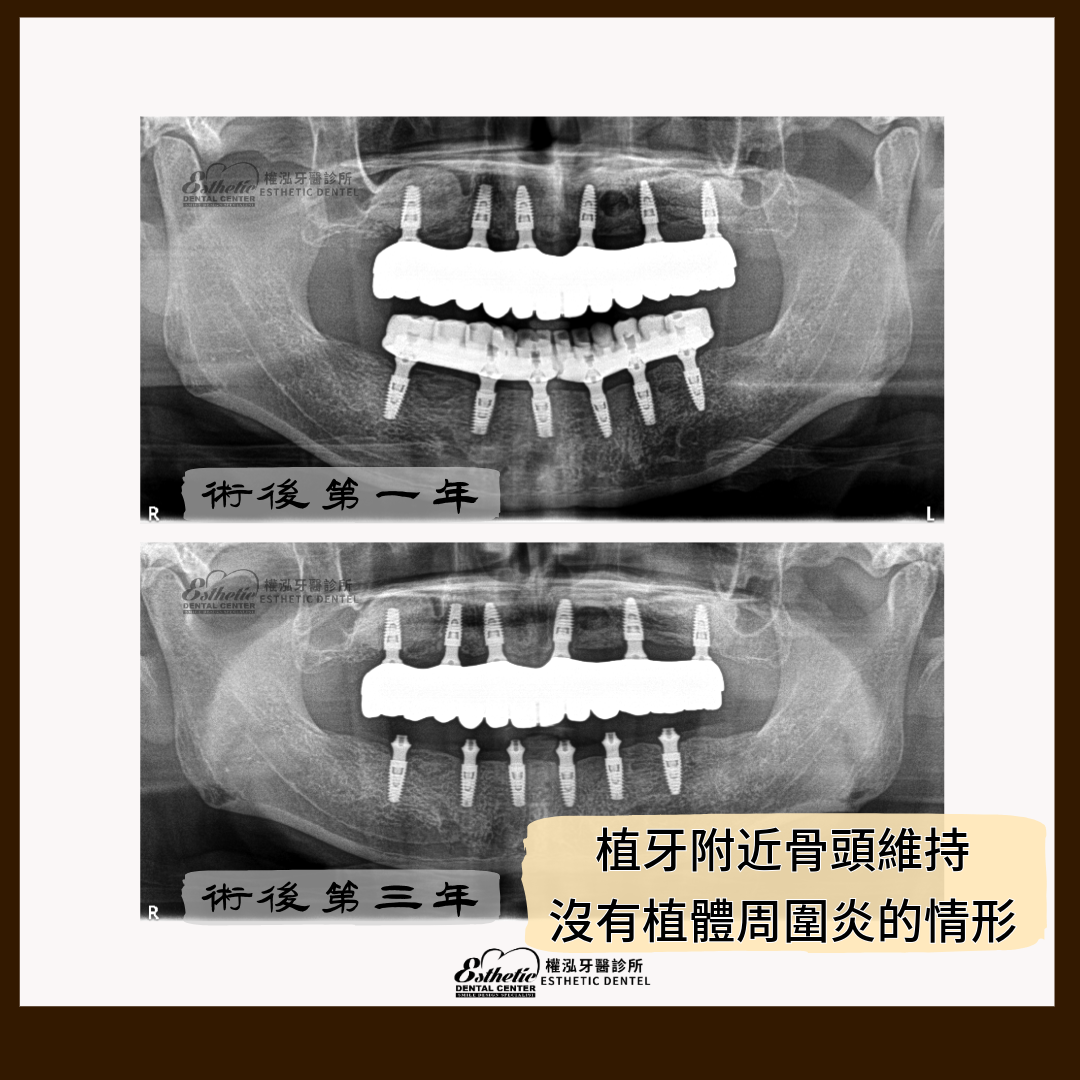

這位患者完成 All-on-6 全口重建已經三年多。從術後到現在,他始終維持著穩定的咬合與自然的笑容。

必要時拍攝 X 光影像,確認植體與骨整合狀況,確保基礎結構穩定。